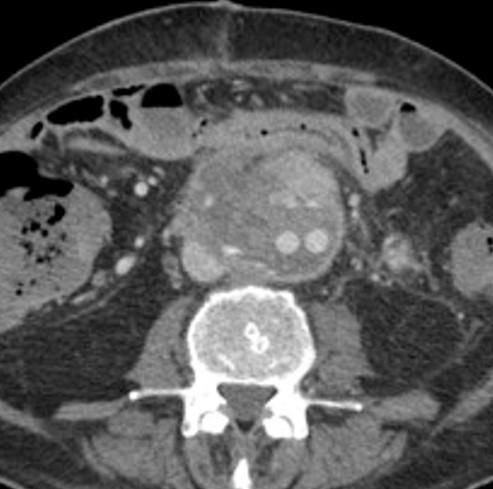

No.150症例10:80歳代 女性

【画像所見のまとめ】

• 大動脈の右側、内膜石灰化よりも外側に、造影効果を有する占拠性病変を認める

• 両側肺野に微小な結節を多数認め、 1週間の経過で増大している

• Intimal type:血管内腔に突出する疣贅様の腫瘤

• 血栓と紛らわしい

• 不均一な造影効果を有する

• Mural type:血管の外側に存在する結節状・三日月状の腫瘤

• 血管新生による造影効果